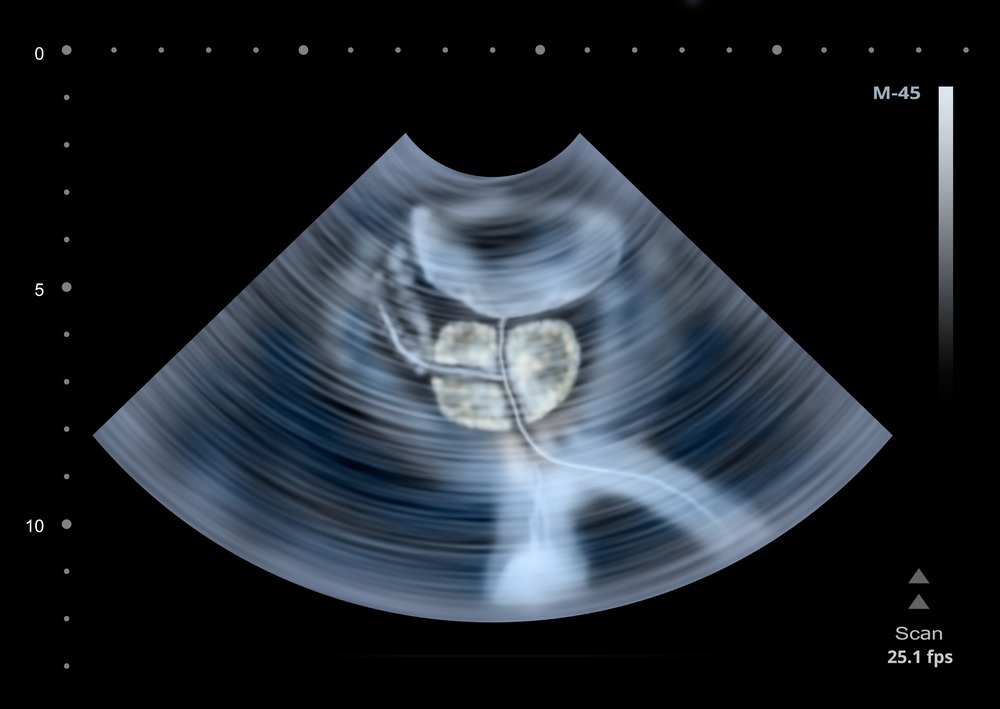

A prostate scan is a non-invasive imaging procedure used to examine the prostate located in the lower abdominal cavity. It also assesses the bladder, measuring its volume before and after emptying, as well as the prostate and seminal vesicles.

A transrectal prostate ultrasound uses a small probe (camera) that is inserted into the rectum for having a closer look at the prostate for medical imaging to check the prostate inside your lower abdominal cavity. This includes bladder with the measurement of bladder volume before and after emptying, prostate, and seminal vesicles.

Prostate ultrasound is a non-invasive (except transrectal scan for the prostate in which a small probe (camera) is inserted into the rectum for having a closer look at the prostate) medical imaging to check the prostate inside your lower abdominal cavity. This includes bladder with the measurement of bladder volume before and after emptying, prostate, and seminal vesicles.

You will be asked to lie down on the scan couch(bed) comfortably. Our well qualified experienced specialist ultrasound Practitioner/Sonographer or Consultant Radiologist will put water-based gel on your lower tummy. Thereafter, they examine all included organs by placing the transducer (camera) over the gel on your lower belly. After completing the first part they will direct you for emptying the bladder (for the wee) and will check the remaining amount of urine in your bladder.